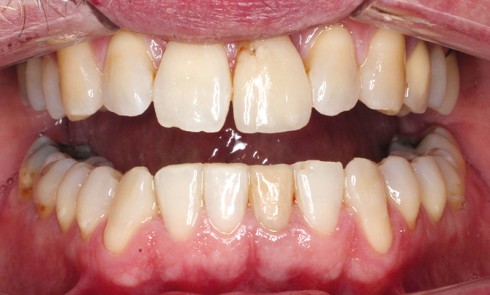

Article réservé à nos abonnés Chronologie du plan de traitement : paro, ortho, implanto

Depuis les travaux de Brånemark, l’implantologie moderne basée sur les données scientifiques offre une option thérapeutique fiable à long terme....